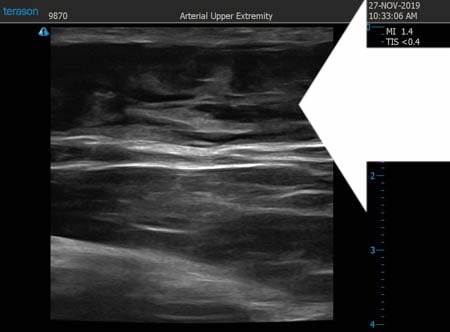

いつものように3Dタッチビュー(超音波)で

皮下脂肪層を評価してみましょう。

上腹部